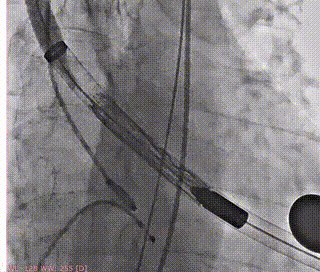

术前造影(左右窦重合体位)

释放支撑臂

支撑臂释放后定位